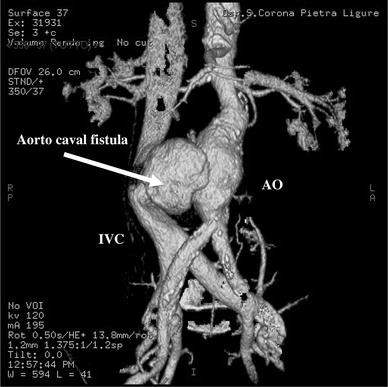

aortocaval fistula (aorta to IVC fistula) can occur spontaneously or from trauma

usually a complication of an abdominal aortic aneurysm (AAA)

may rupture into IVC » causinf massive A-V fistula OR rupture into duodenum w upper GI bleeding (RARE)